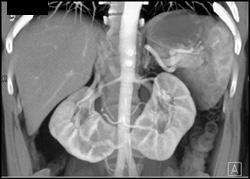

Ct Urogram